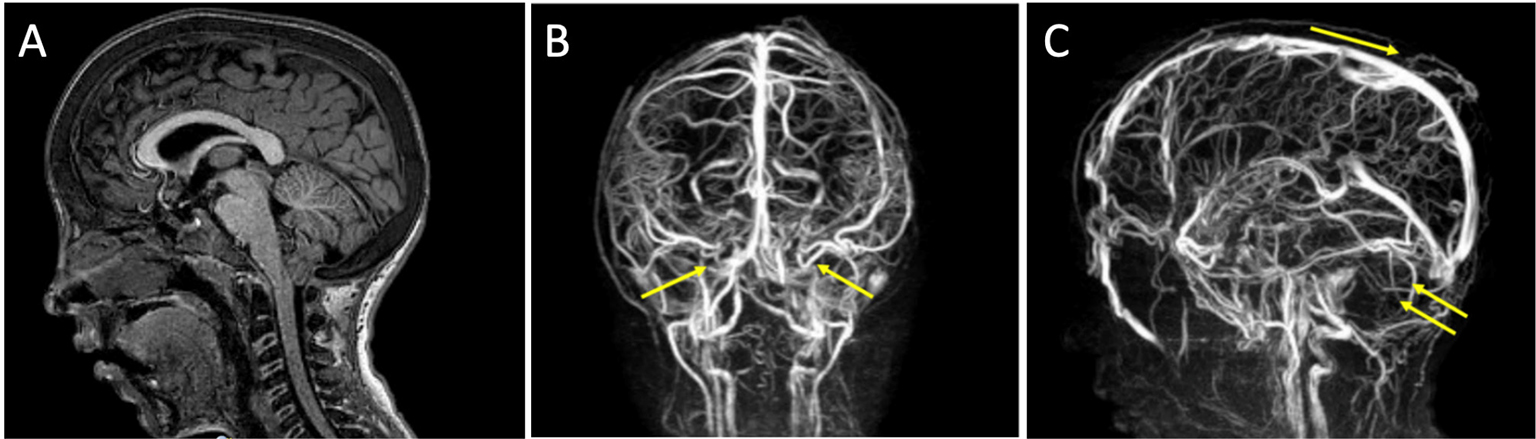

A Chiari I malformation was diagnosed by MRI (Fig. 3A). No syringomyelia was seen at the level of the medulla. Venous sequences by MRI angiography showed the absence of signal at the level of the transverse sinuses, with the presence of collateral venous circulation (Fig. 3B, C), which could lead to intracranial hypertension due to reduction of liquor reabsorption in the venous system.

Fig. 3 - Case 3. A) Chiari type 1 malformation evident by MRI. B, C) Venous sequences by MRI angiography showing the absence of signal at the level of the transverse sinuses, with the presence of collateral venous circulation. MRI = magnetic resonance imaging.